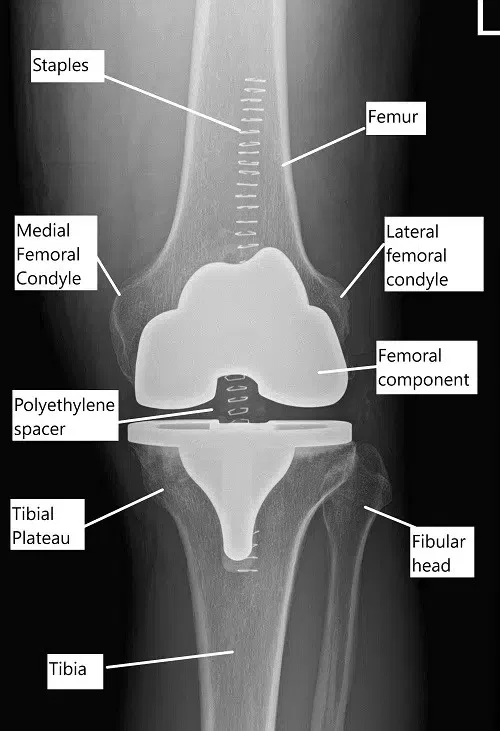

Radiografía postoperatoria que muestra un reemplazo total de rodilla.